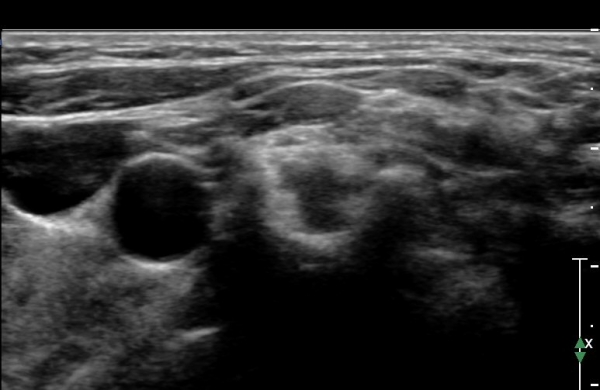

ŽÃËÀÚ¸¦ Á¶±Ý ¸»´ÜÀ¸·Î À̵¿ÇÏ¿© Àü»ç°¢±Ù°ú Á߻簢±Ù »çÀÌ¿¡¼­ »ó¿Ï½Å°æÃÑÀÇ Àú¿¡ÄÚ ºÎÁ¾ÀÌ °üÂûµÊ                  (»çÁø 2, 3).

¸ñ ¾Õ ¿ÜÃø¿¡¼­ Á¦5, 6 ½Å°æ±Ù Á¾´Ü¸é°Ë»ç¿¡¼­ Á¦5, 6 ½Å°æ±ÙÀÇ Àú¿¡ÄÚ ºÎÁ¾(4,5mm, 6.5 mm)ÀÌ

°üÂûµÇ°í »çÁø 4,5 ) °ÇÃø(»çÁø 6, 7)(2.4mm, 3.1mm)°ú ºñ±³ÇÏ¸é ¾à 2¹èÀÌ»ó ºÎÁ¾ÀÌ ¶Ñ·ÇÇÔ.